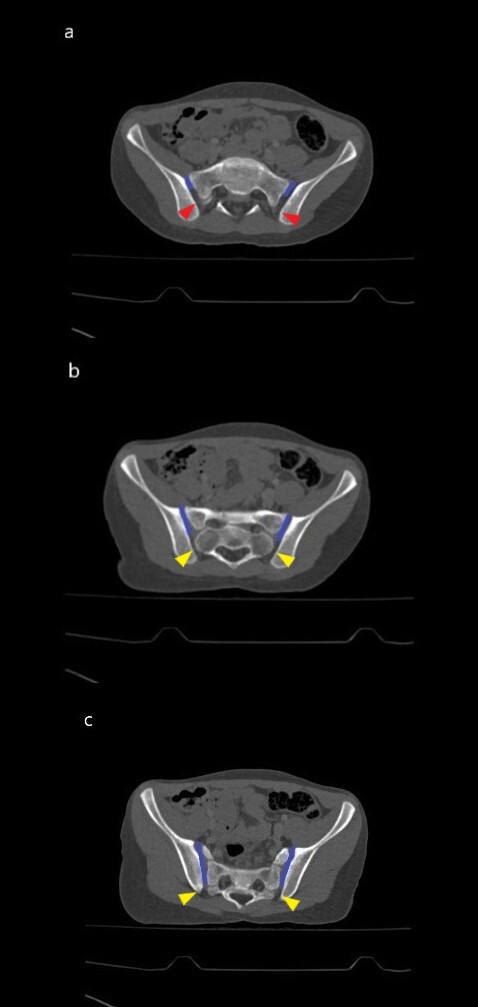

Each study image was assessed by the two blinded radiologists (first author ED and third author SA). Each radiologist independently evaluated the CT images on the coronal, axial and sagittal planes. In case of contradictory results, the images were evaluated together by both radiologists. Imaging evaluations were made at the workstation with a high-resolution medical monitor in soft-tissue window [Windows width (WW): 400 Hounsfield unite (HU), windows level (WL): 50 HU], bone window (WW: 1800 HU, WL: 400 HU) as well as the lung window (WW: 1500 HU, WL: -600 HU) to distinguish air more clearly from soft tissue and bone. The presence of gas (i.e., air) was considered positive for VP in the SIJ (Figure 1).

Patient results were classified according to age groups (0-4 years old, 5-8 years old, 9-11 years old, 12-14 years old, 15-17 years old) as well as gender (male, female). Data according to the presence of SIJ VP were enlisted as right, left and bilateral (Figure 2).

The SIJ is the body’s largest joint.14 Roughly, the upper third of the joint is a syndesmosis (fibrous joint linked by a strong membrane or ligaments), the middle third symphysis-like and the lower third the synovial.15 However the synovial part is not limited to only the lower segment. It continues towards superior in an oblique course along the anterior part. In other words, most the superior part of SIJ is syndesmosis but a small part is synovial.16 This anatomical information is important for understanding and discussing the research on the right basis. Since the VP effect is in the synovial part, the gas is formed in this part of the joint Figure 5.16–19